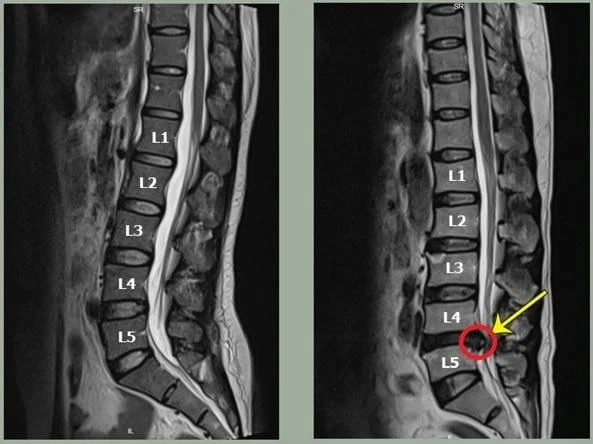

![]() |

Hình ảnh đường cong cột sống thay đổi trong bệnh thoát vị đĩa đệm vùng cột sống thắt lưng. Ảnh: BSCC |